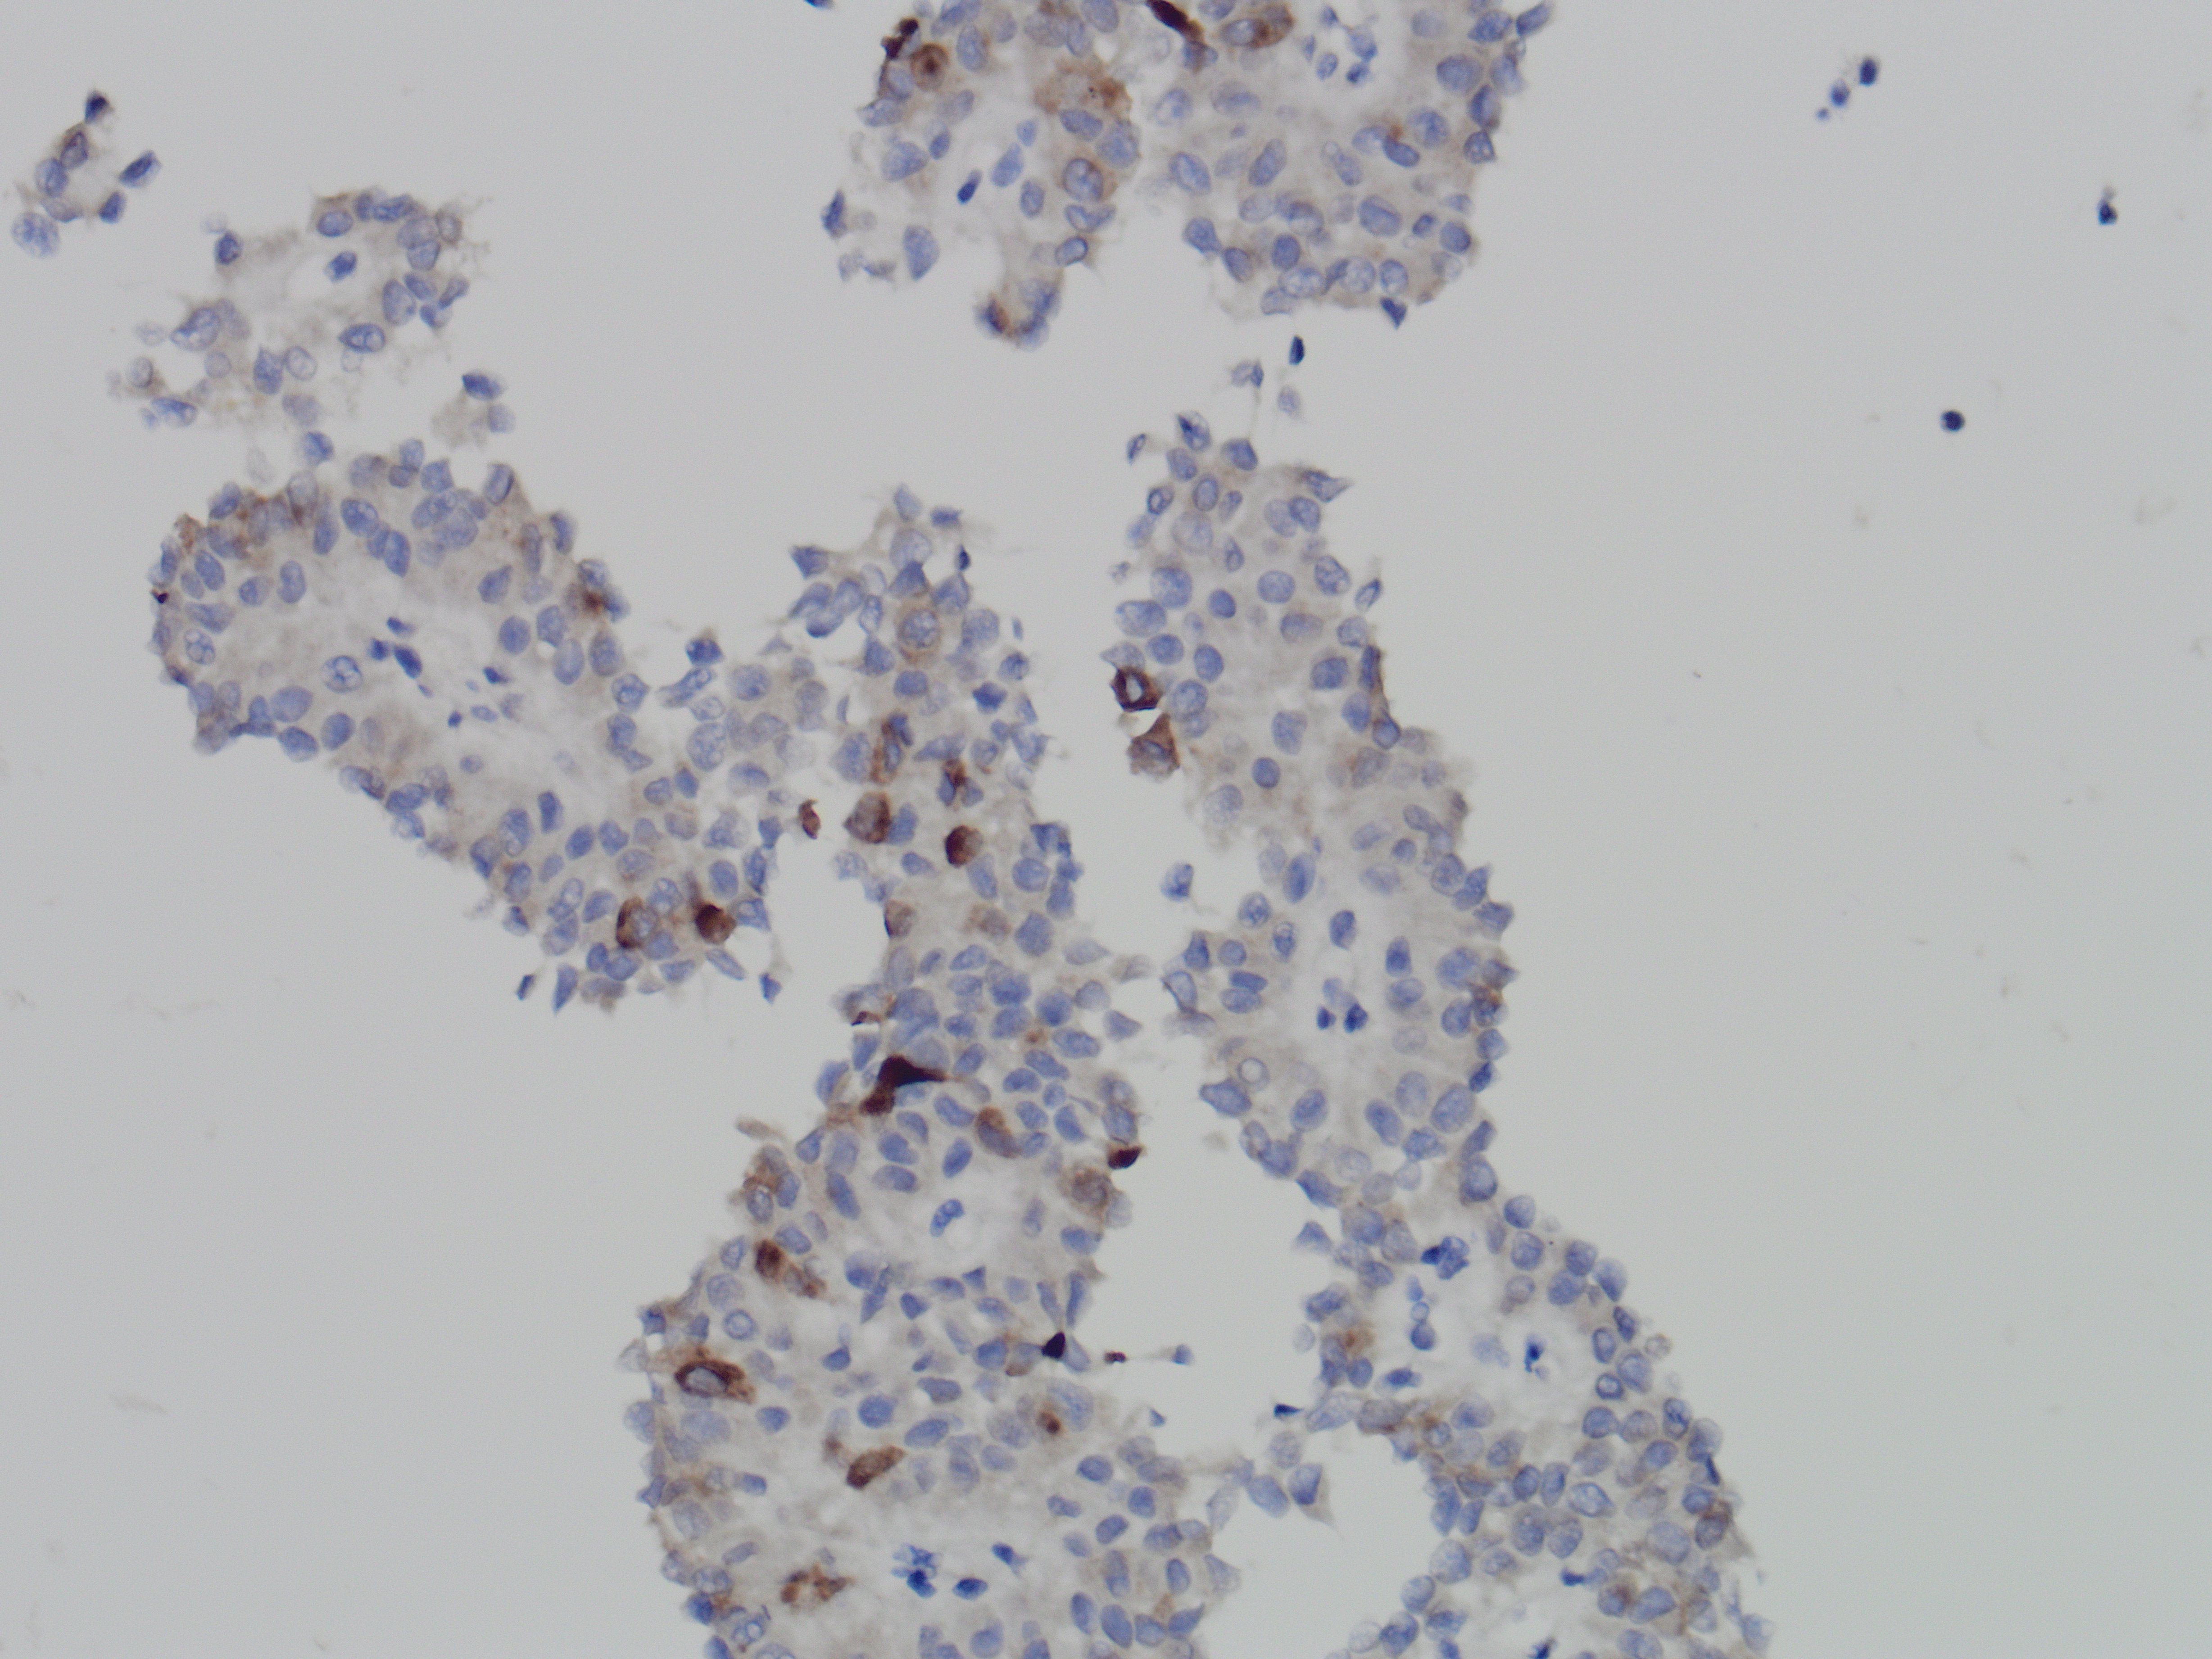

The specimen is richly cellular and consists of abundant monomorphic cuboidal nonmucinous cells, which are arranged as loosely cohesive groups and isolated cells (Figure 1). The neoplastic cells show delicate vacuolated cytoplasm with indistinct cell borders (Figure 2). These solid nests of loosely cohesive cells forming a cuff surrounding blood vessels result in a pseudopapillary architecture, which are well appreciated in the smear and cell block (Figure 3 and 4).

The differential diagnoses include pancreatic neuroendocrine tumor, solid pseudopapillary neoplasm and acinar cell carcinoma. By immunocytochemistry, the neoplastic cells show diffuse nuclear positivity for beta-catenin (Figure 5) and membranous positivity for CD10 (Figure 6). Also, the tumor cells are focally and weakly positive for synaptophysin (Figure 7). Taken together, the final diagnosis is solid-pseudopapillary neoplasm.